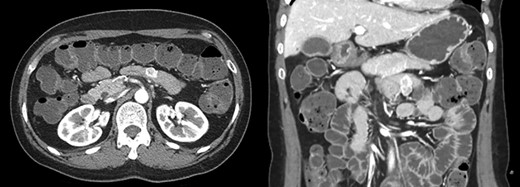

A 46-year-old single woman presented to the surgical department with intermittent abdominal pain and melena for 1 month. She had no significant medical history. The physical examination and all routine laboratory investigations were unremarkable. Abdominopelvic computed tomography (CT) showed a 2.3 cm sized well-defined heterogenous enhancing mass in the proximal jejunum and GIST was strongly suspected (Fig. 1).

Abdomen CT showed a 2.3 cm sized well-defined heterogenous enhancing mass in the proximal jejunum and GIST was strongly suspected.